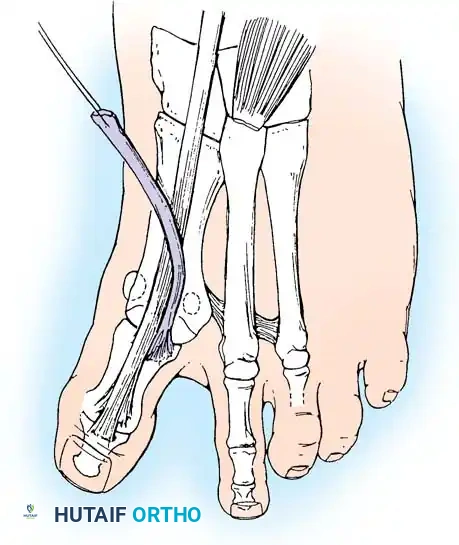

FIBULAR (LATERAL) SESAMOIDECTOMY: DORSAL APPROACH

• If after complete adductor hallucis release and preferably after a lateral capsular release, a fi bular sesamoidectomy is needed to correct the valgus deformity of the great toe fully, it should be done at this time.

• Adequately separate the fi rst and second metatarsal heads for exposure.

• Plantar fl ex the metatarsophalangeal joint 10 to 20 degrees, which reduces tension on the sesamoids.

• Grasp the fi bular sesamoid with a small Kocher clamp or sturdy tissue forceps, and pull it laterally into the intermetatarsal space (Fig. 78-20).

• Release the intersesamoid ligament. When this ligament has been incised, bring the fi bular sesamoid into the intermetatarsal space, where its removal is straightforward. Care must be taken when incising the intersesamoid ligament to avoid severing the fl exor hallucis longus tendon immediately plantar to it. If the tendon is severed, it probably should not be repaired at this level; loss of the tendon causes little if any functional impairment, and

An alternative to fi bular sesamoidectomy was recommended by Mauldin, Sanders, and Whitmer, who released part or all of the fl exor hallucis brevis lateral head at its insertion into the fi bular sesamoid. This release of the sesamoid is needed only if fi xed valgus remains after the adductor hallucis has been released, a lateral capsulotomy has been performed, and the fi bular sesamoid has been mobilized. Also, in this situation, a metatarsal osteotomy may be needed, rather than a fi bular sesamoidectomy. Performing both may cause hallux varus.

FIBULAR SESAMOIDECTOMY: PLANTAR APPROACH

• If a plantar approach (Fig. 78-21A) is chosen for fi bular sesamoidectomy, have an assistant hold the ankle dorsifl exed, and use a headlight for seeing into the full depth of the wound. Avoid the fl exor hallucis longus tendon and the neurovascular bundle to the fi rst web space.

• Flex and extend the hallux, and inspect the radiograph to locate the sesamoid. Beginning 1 to 1.5 cm distal to the metatarsophalangeal joint, make a longitudinal incision in the plantar surface of the foot, extending the incision proximally 3.5 to 4 cm between the fi rst and second metatarsals.

• If the fi bular sesamoid requires excision, it usually is subluxed.

• When the skin and fascial septa within the forefoot pad have been separated, insert a small self-retaining retractor.

• Using small, blunt-tip dissecting scissors, identify the neurovascular bundle to the fi rst web space, and retract it laterally or medially, depending on the position of the sesamoid (Fig. 78-21B).